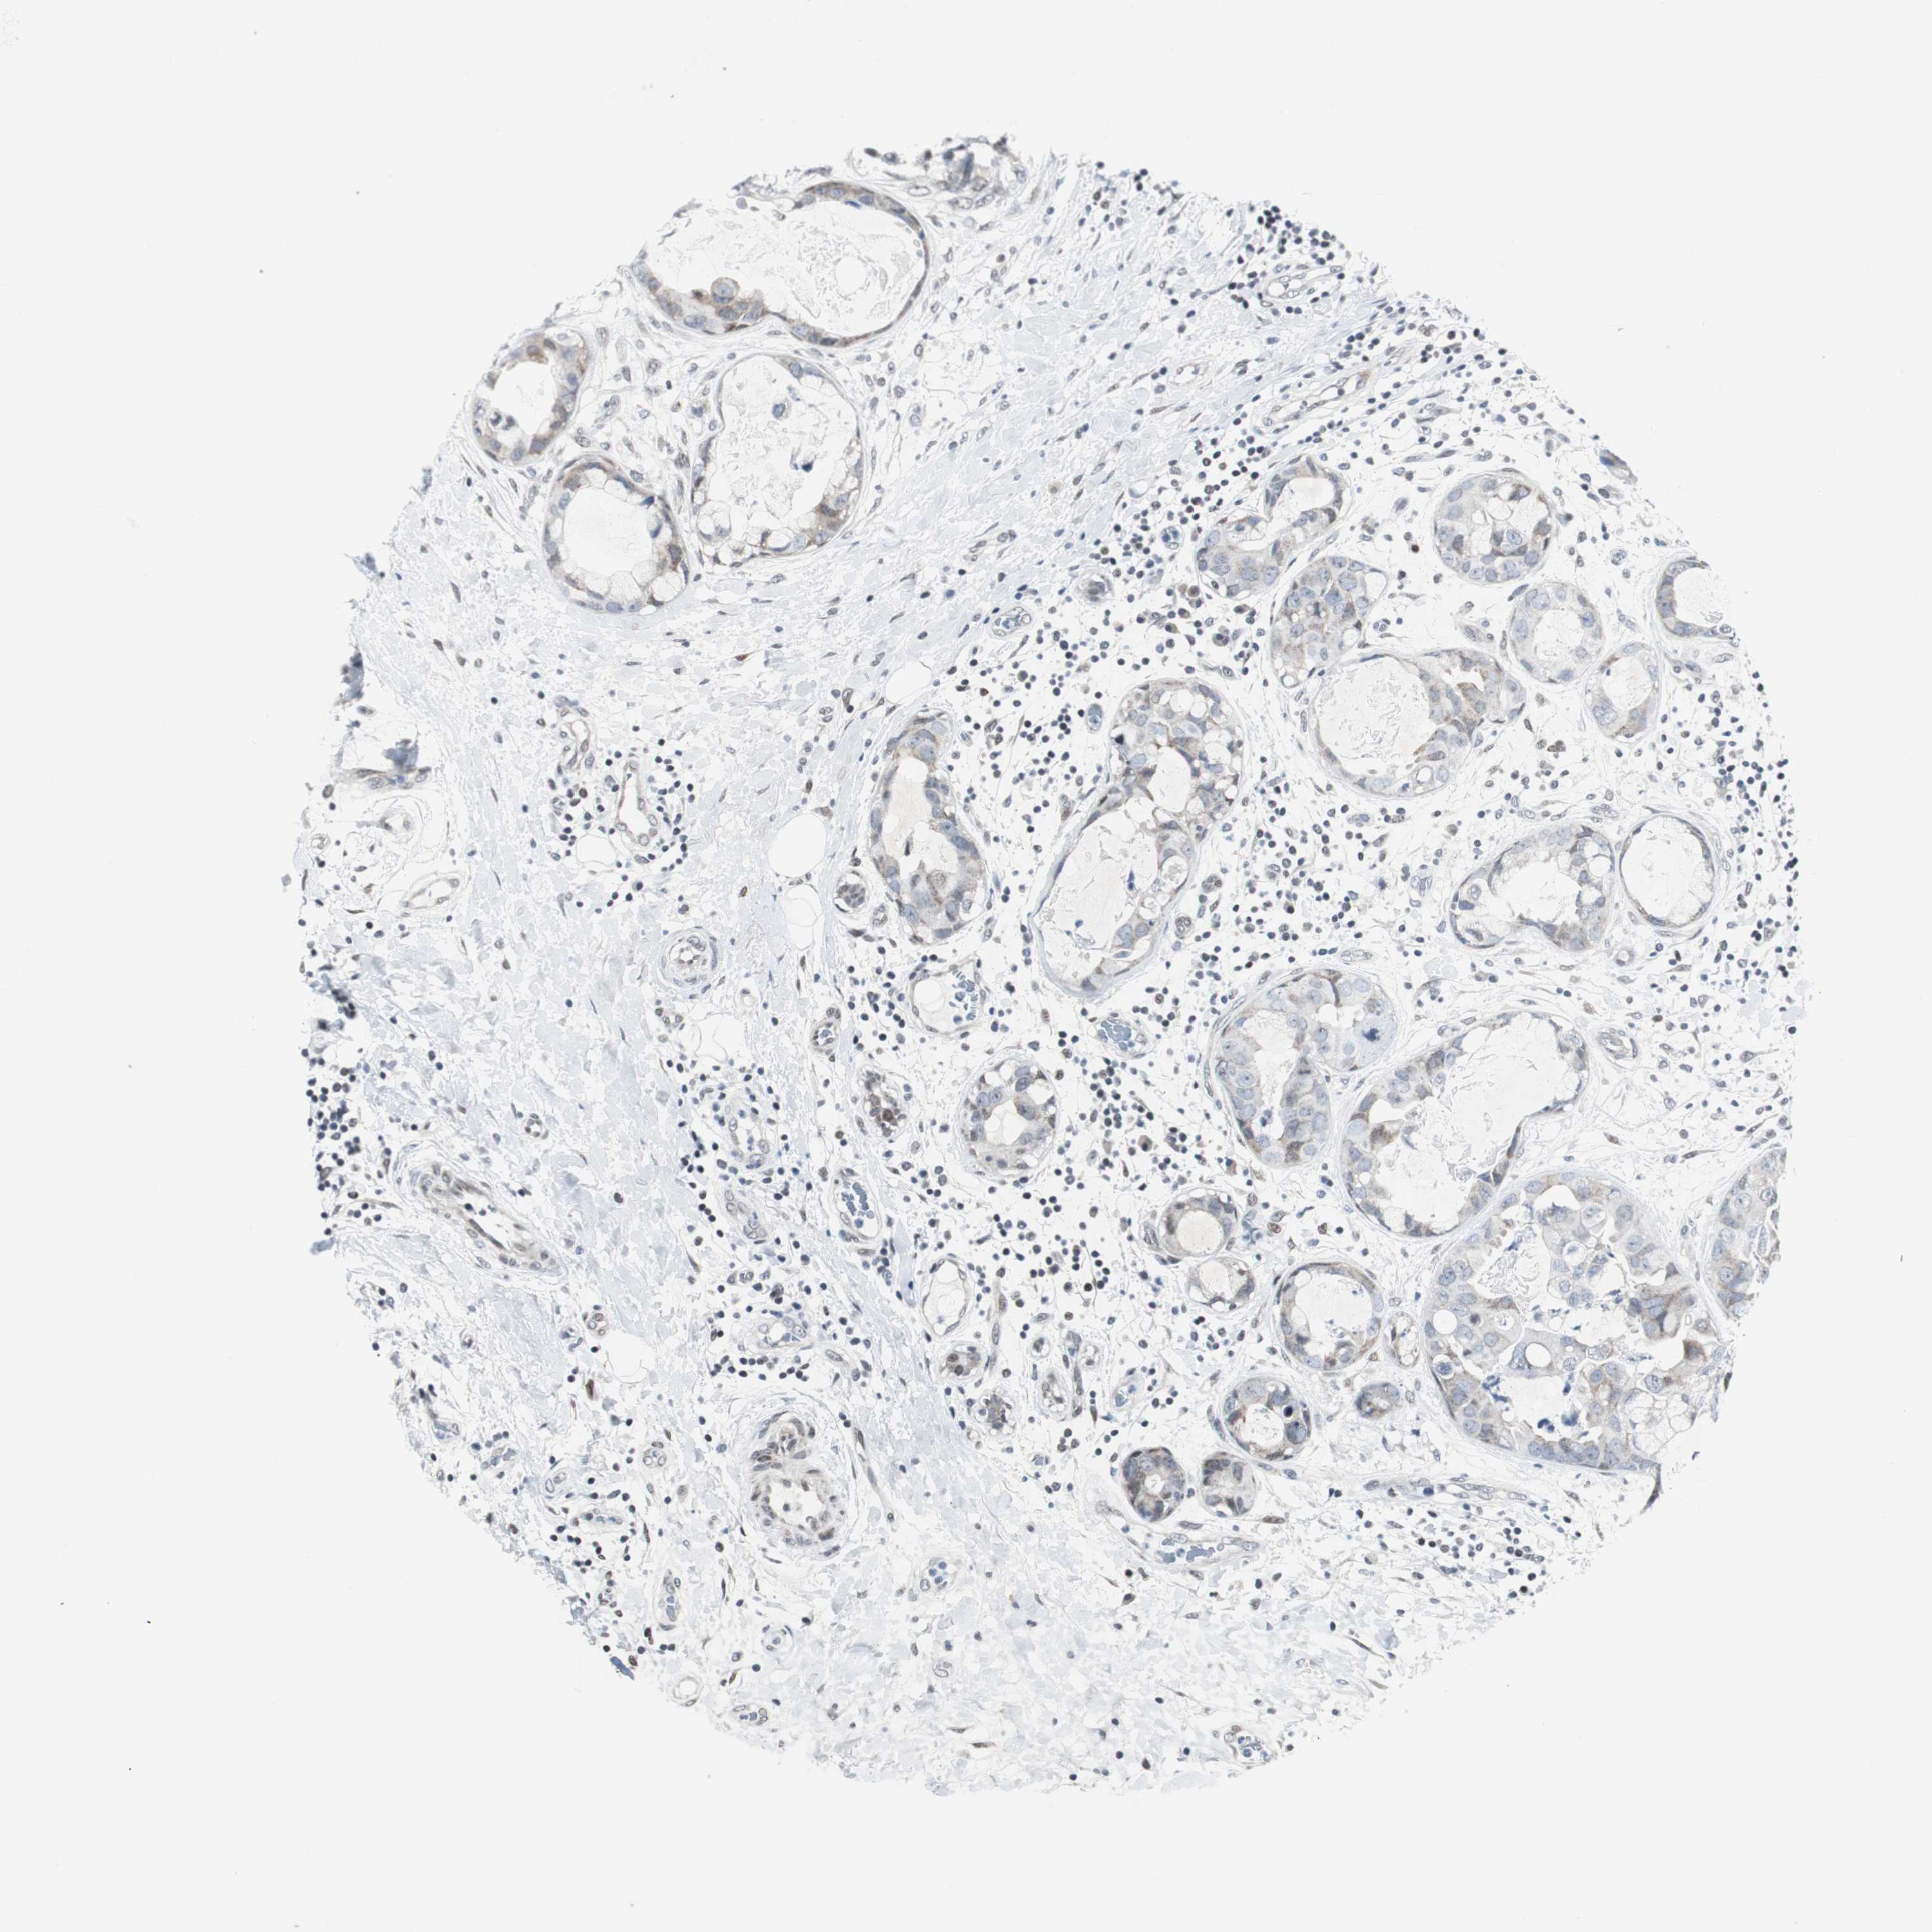

BRCA TCGA BRCA VALIDATION PROTEIN EXPRESSION

ANTIBODIES

AND

VALIDATION